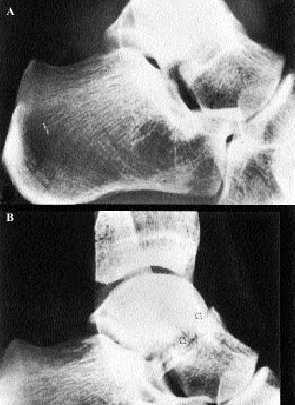

Radiología

Suelen ser suficientes para la confirmación del diagnóstico las proyecciones habituales de tobillo anteroposterior, y más útil la lateral, y las proyecciones del pie, dorsoplantar y oblicua. Como ocurre con la mayoría de las fracturas no desplazadas, un vistazo rápido a la radiografía se seguirá de un error diagnóstico; obsérvese la radiografía lateral de tobillo de la figura 13, que muestra claramente la fractura de cuello de astrágalo. Si esta radiografía la vemos pensando que el paciente sufre un esguince de tobillo, centraremos la atención en los maléolos y la fractura quedará sin diagnosticar. Nuevamente es esencial la sospecha clínica previa. La radiografía lateral de tobillo de la figura 14A muestra una imagen que fácilmente podría juzgarse como normal; en este caso la sospecha clínica aconsejaba obtener otra proyección radiológica oblicua (fig. 14B).

Fig. 13. Fractura del cuello del astrágalo.

Fig. 14 A y B. Fractura del astrágalo.